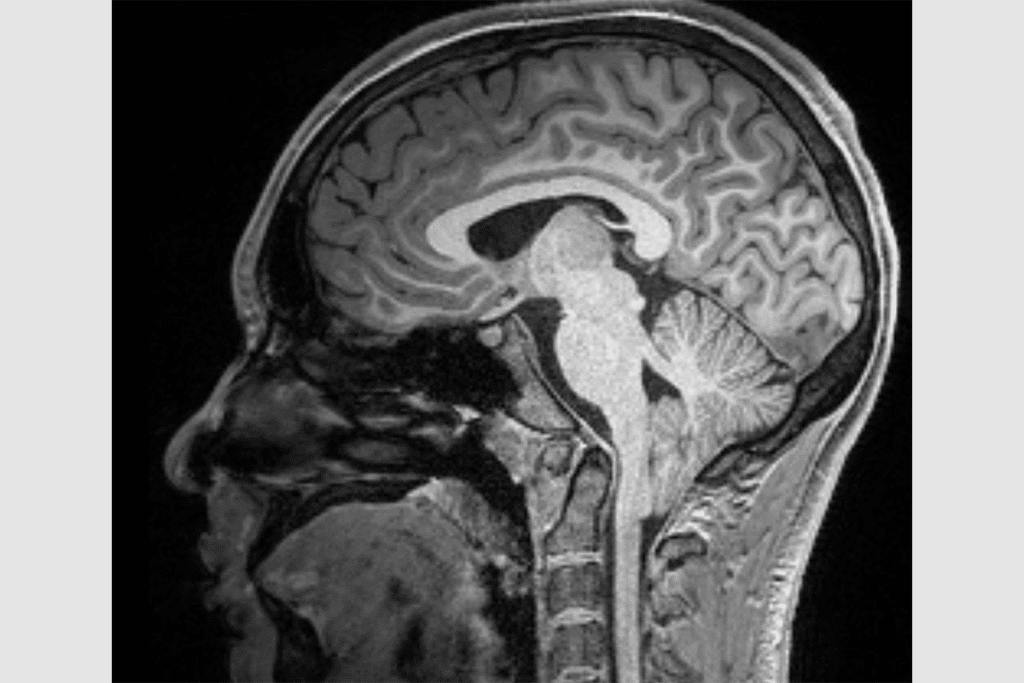

Advanced Imaging Techniques for Detection

Magnetic Resonance Imaging (MRI) is key in finding Chiari malformation. It shows us the cerebellum and brainstem clearly. This helps us see how bad the malformation is.

We use high-detail MRI scans to see how far the cerebellum is moved. We also look for other problems like syringomyelia or tethered cord syndrome.